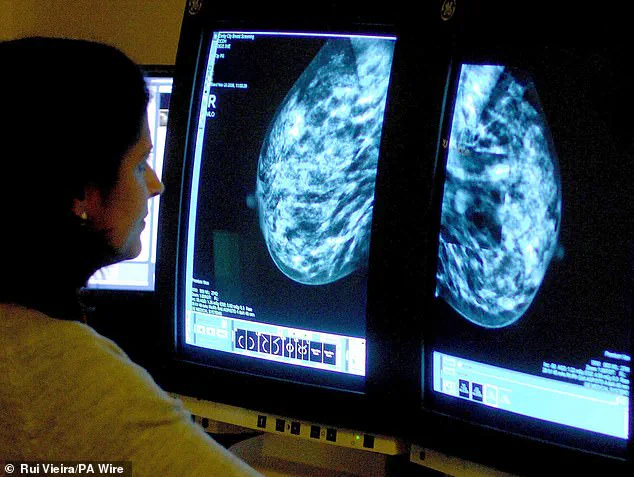

Routine screening programs, such as those offered to women aged 50–70 in the UK, remain a cornerstone of public health strategy.

These programs, which utilize mammography, have been shown to reduce mortality rates by up to 20% in participating populations.

However, the rising incidence among younger women has prompted calls for expanded screening guidelines.

Experts from the European Society for Medical Oncology are currently reviewing data to determine whether earlier or more frequent screenings for women under 50 could mitigate the growing burden.